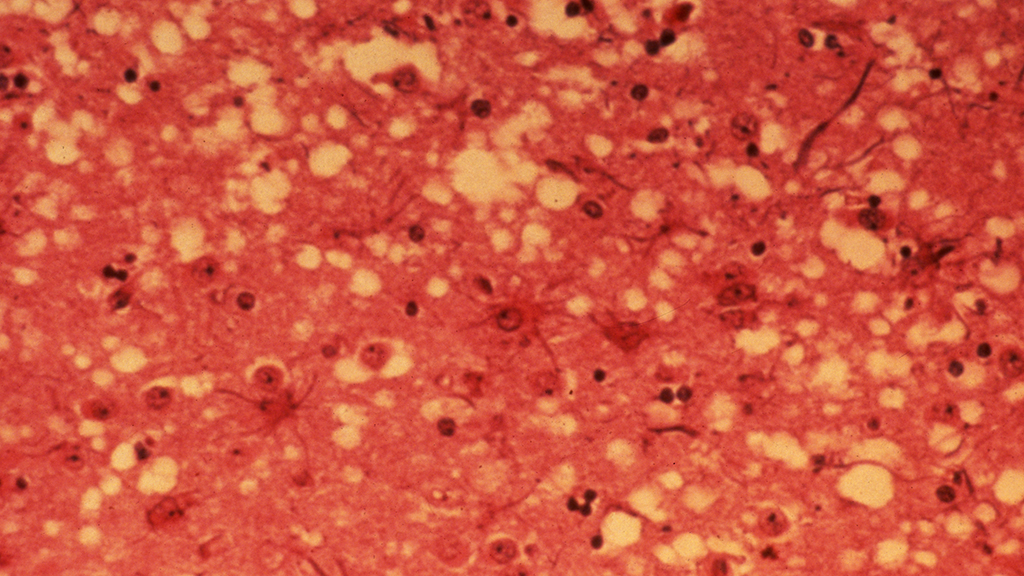

This case centers on a fictional group of young adults who studied abroad together in Scotland as college students. A number of them develop disease symptoms and die a few years after the trip. The cause of death is determined to be a prion disease. Applying information from pre-reading assignments as well as from the case itself, students propose hypotheses as to which prion disease was the most likely cause of death and how it was acquired. In the final section of the case study, students are asked to imagine that this occurred on their campus and write an essay explaining the disease in the case study to a general audience and why they should or should not stay on campus. The case was designed for an upper-division undergraduate course in the biochemical basis of disease and is intended to introduce students to prions and the diseases caused by this infectious protein. It could also be used in undergraduate courses dealing with infectious disease, global health, physiology, or biochemistry.